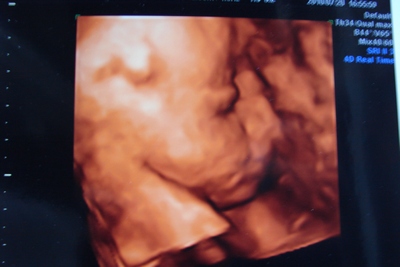

Várjuk a 4D-t, várjuk a 4D-t!!!

Jaj, de nem a Shrekket, azt már láttam és különben sem tudnál átverni vele, mert az csak 3D-s.

További szépséges és jó kismamiságot!